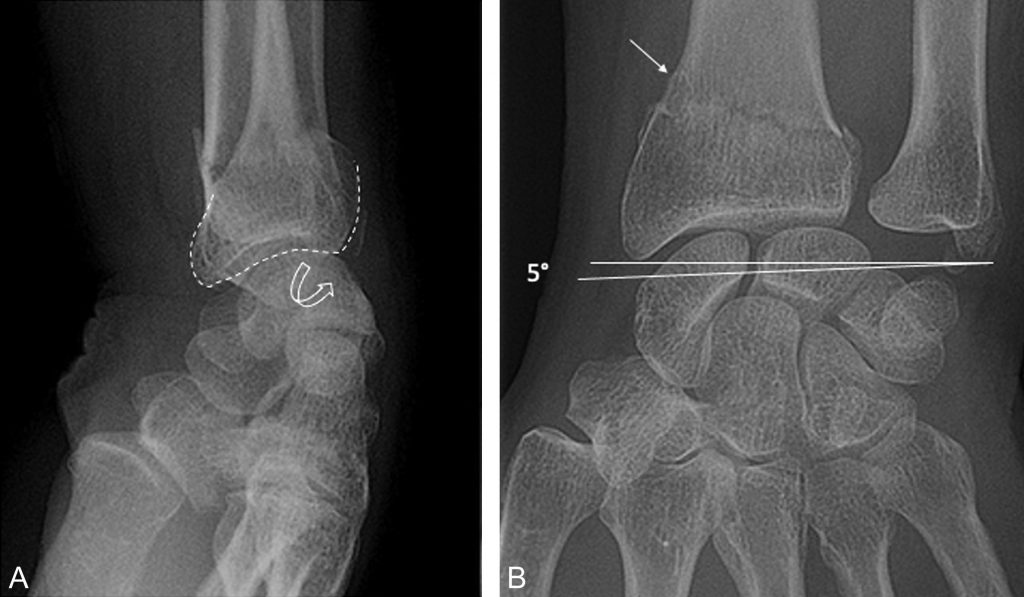

Fracture de Pouteau-Colles (figure 77.2) :

- fracture sus-articulaire, à distance de l’interligne radiocarpien ;

- bascule postérieure du fragment distal ;

- horizontalisation de la ligne bistyloïdienne (index radio-ulnaire).

Fig. 77.2 Fracture de Pouteau-Colles : radiographies de profil (A) et de face (B) du poignet gauche.

Fracture extra-articulaire de l’extrémité distale du radius (flèche) avec horizontalisation de la ligne bistyloïdienne et bascule postérieure de l’extrémité distale. Noter la fracture de la base de la styloïde ulnaire associée (appelée alors fracture de Gérard-Marchant).

Source : CERF, CNEBMN, 2022.